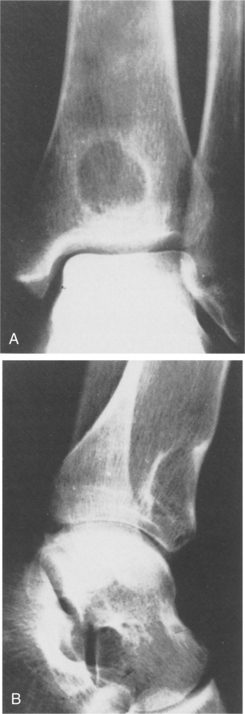

Those found in the long bones are usually in the diaphysis, although as with most tumors, they can be seen elsewhere (Fig. 26-5). The histologic makeup of osteoblastoma is very similar to that of an osteoid osteoma. In fact, sometimes it is size alone that differentiates the two, with osteoblastoma being the larger. The lesions are osteolytic and have a sclerotic border.

Figure 26-5 Genuine (conventional) osteoblastoma of the tibia in a 24-year-old woman. Anteroposterior (A) and lateral (B) radiographs show a round radiolucent lesion with slightly sclerotic borders at the lower and anterior aspect of the tibia. (From Gitelis S, Schajowicz F: Osteoid osteoma and osteoblastoma, Orthop Clin 20:320, 1989.)